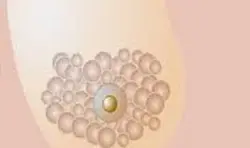

Memenin yapısını en doğru şekilde değerlendiren görüntüleme teknikleriyle erken tanıda güven

Meme Radyolojisi